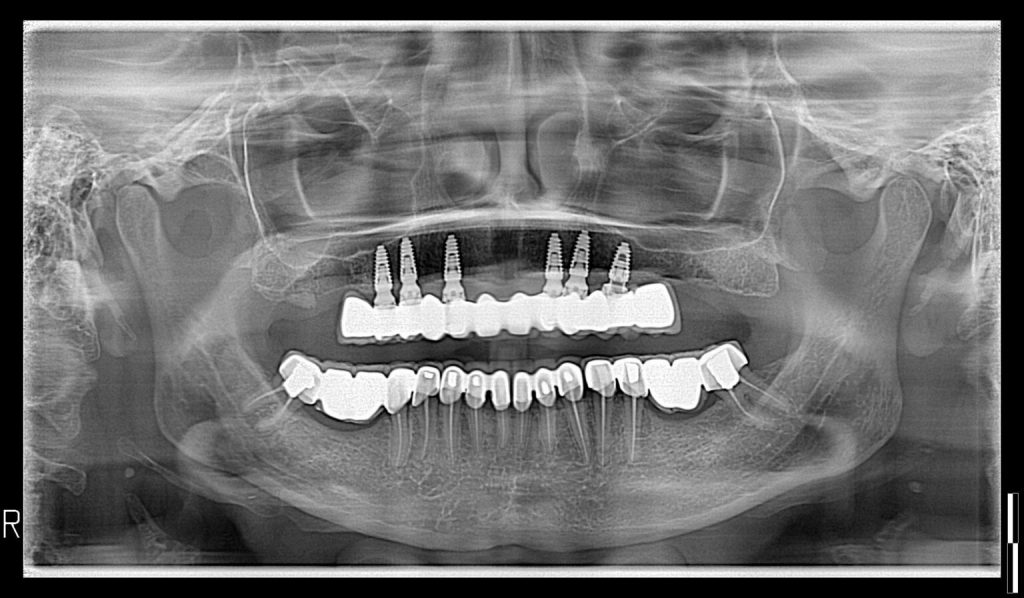

Calidad de imagen excepcional